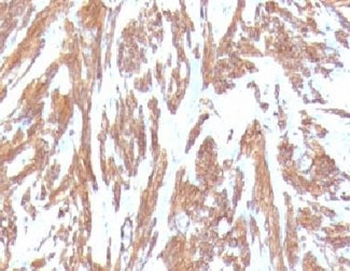

IHC: Formalin-fixed, paraffin-embedded Leiomyosarcoma stained with Smooth Muscle Actin antibody (clone SPM332).